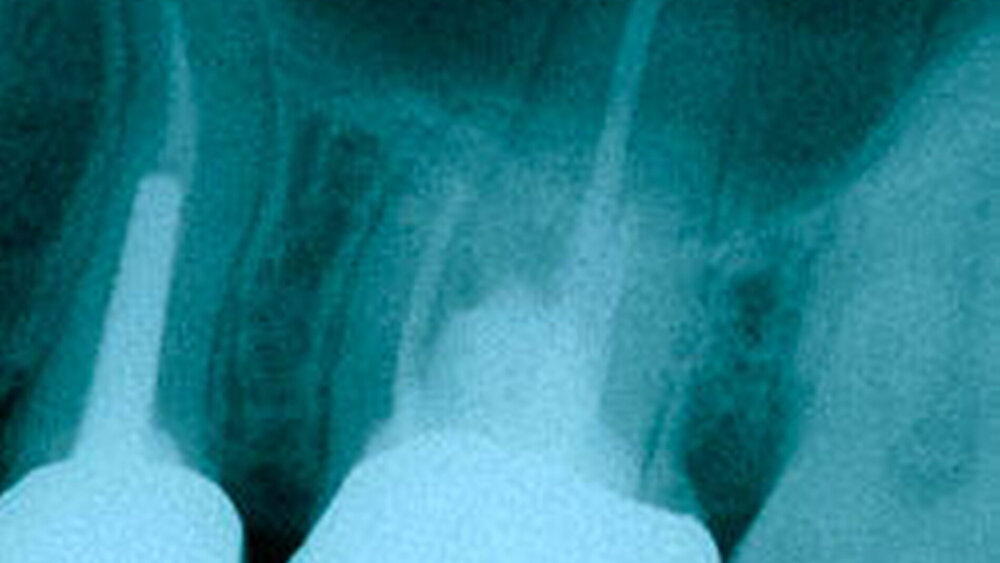

Im Röntgenbild ist an Zahn 26 zentral unterhalb der Krone eine große Aufhellung im Sinne einer Perforation erkennbar (Abbildung 9). Die vom Vorbehandler eingebrachten Wurzelkanalinstrumente scheinen sämtlich im palatinalen Kanal beziehungsweise im Bereich der Perforation platziert zu sein.

Wiederum ist zentral im Bereich unter der Krone eine relativ große Aufhellung im Sinne einer ausgedehnten Perforation zu erkennen (Pfeil Abbildung 11). Die Instrumente sind weitgehend auf korrekte Arbeitslänge eingebracht, lediglich im mesiobukkalen Kanal soll nach endometrischer Bestätigung eine Reduktion der Arbeitslänge um 1 mm erfolgen.